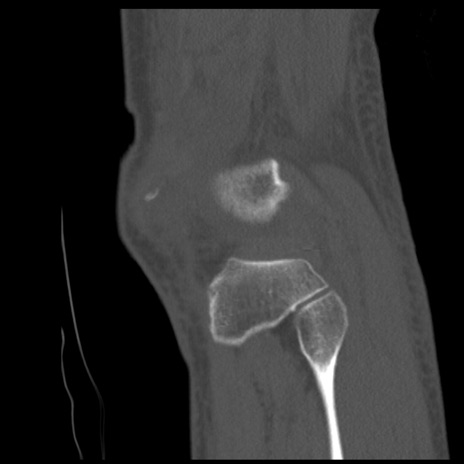

症例28 右膝関節CT(矢状断像)

右膝関節CT